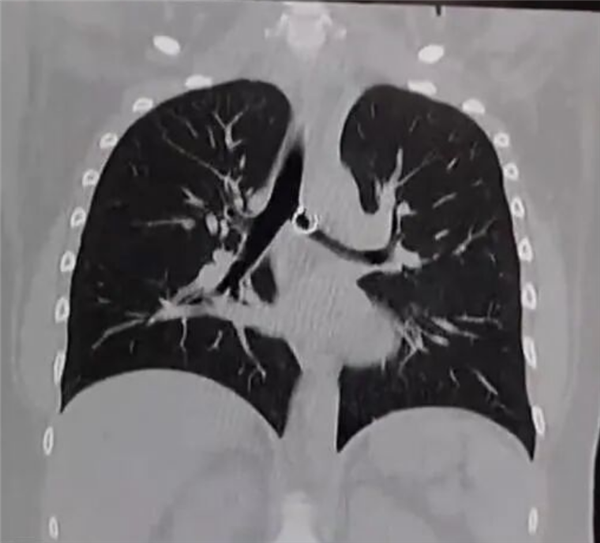

据悉,莫妮卡最初将咳嗽归咎于普通感冒,并未重视,期间发现佩戴的鼻环丢失,也只当是无意中掉落,从未将两者关联。直到咳嗽持续一个月,甚至影响正常生活,她才就医检查,X光和CT扫描清晰显示,其肺部有一枚金属异物,正是她丢失的鼻环。医生检查后直言情况极度危险,鼻环已深深嵌入肺部组织,一端的金属小球距离肺主动脉仅0.5毫米,一旦移位或被触碰,就可能刺破主动脉,导致瞬间大出血,几乎没有抢救时间。

据推测,这枚鼻环大概率是莫妮卡在睡眠中无意识吸入,经气管进入肺部后逐渐移动到危险位置。

由于异物位置过于凶险,常规支气管镜手术被迫终止,医院紧急组织多科室专家会诊,最终通过胸腔镜微创手术,在精准导航下小心翼翼将鼻环完整取出,全程未损伤主动脉,术后莫妮卡恢复良好,咳嗽症状迅速消失,很快康复出院,但她着实被吓到了,坚决称以后再也不佩戴鼻环。医生提醒,佩戴鼻环等穿刺饰品时,需选择固定牢固、无松动部件的款式,睡眠时尽量取下;若出现持续咳嗽、呼吸困难等异常症状,切勿忽视,需及时就医,同时若有饰品丢失,应告知医生可能存在异物吸入风险,避免小隐患酿成致命危险。